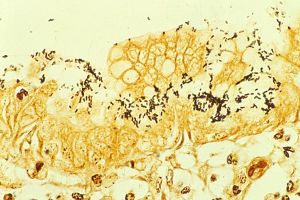

Immunohistochemical staining of H. pylori from a gastric biopsy | |